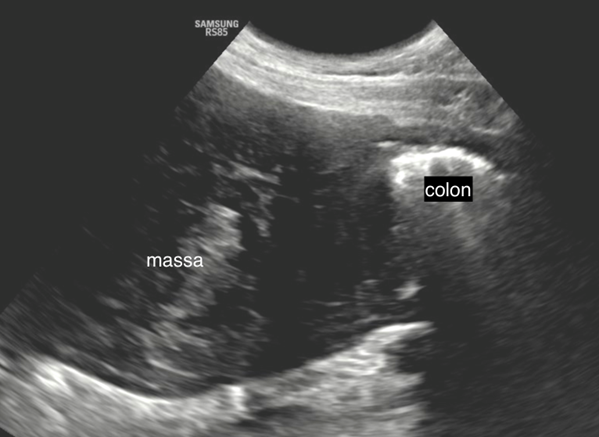

Bij echografisch onderzoek wordt caudaal in de peritoneale holte een grote, goed begrensde, afgeronde massa (ca. 3,3 x 5,2 cm) gevonden met een heterogeen echoarme structuur. De massa ligt dorsaal tegen de wervelkolom aan en maakt contact met de blaas en het colon. Er is een matig massa-effect zichtbaar waarbij het colon naar links verplaatst wordt (fig. 1).

Fig. 1: echobeeld met convexe transducer van de massa naast het colon.